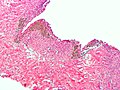

Criteria - need at least 2 / 3 for the diagnosis:[13]

- Endometrial glands - endometrial glands are classically: circular, with nuclei that are hyperchromatic & cigar-shaped.

- Endometrial stroma - endometrial stroma is classically: cellular and hyperchromatic (may resemble a lymphocytic infiltration on low power).

- Hemosiderin-laden macrophages - light brown, may be granular.

- Endometriosis may mimic cancer[15] - see images below.

Mimicking cancer: